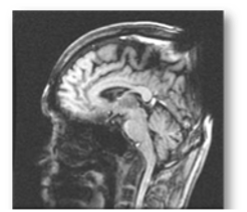

MRI検査

強力な磁場と電波を利用して体内の臓器や血管、神経などを詳細に描き出す検査です。放射線を使用しないため被ばくの心配がなく、安全に実施できます。脳や脊椎、関節、腹部など幅広い領域の精密検査が可能です。検査中は大きな音がしますが、リラックスして受けていただけるよう耳栓やヘッドホンを用意しています。

MRI検査には20~60分の時間を要します。脳内腫瘍をはじめ、感覚などの神経系、手足の関節、その他腫瘍が疑われる部位の軟部組織の描出を得意としています。また、造影剤を使用せずに脳や頸部の血管を描出することも可能です。さらに、CTに比べて脳梗塞の診断に優れており、より早期かつ正確な評価が可能です。

MRIの欠点として、動く臓器や検査中の体動に弱く画像が乱れやすい点があります。強い磁力を使用するため、金属は種類により制限があり、時計、携帯電話、磁気カードは故障したり使えなくなってしまいます。化粧品やカラーコンタクトなども安全のため外していただきます。